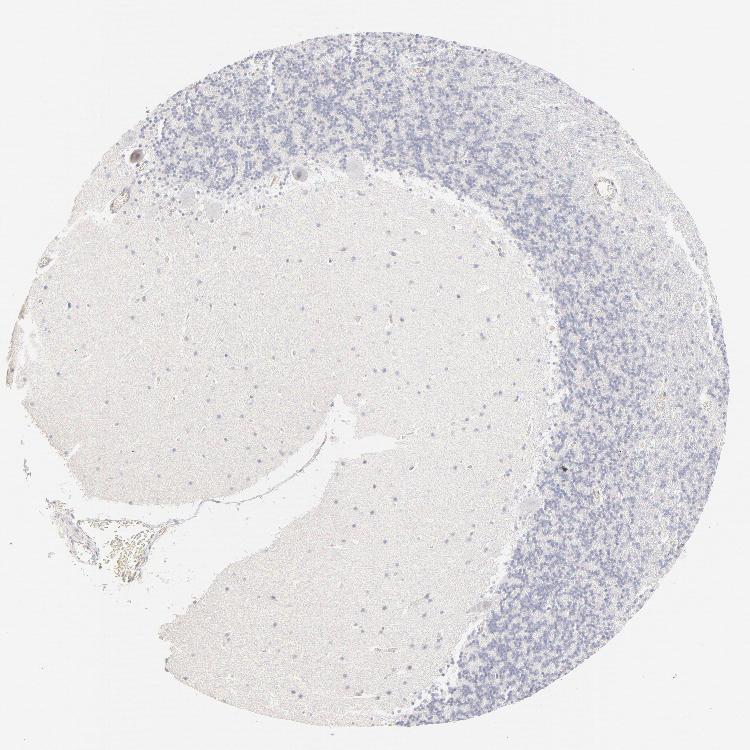

BRAIN CEREBELLUM Show tissue menu

CEREBELLUM - Expression summary

CEREBELLUM - Antibody stainingi

Antibody staining in the annotated cell types in the current human tissue is reported as not detected, low, medium, or high, based on conventional immunohistochemistry profiling in selected tissues. This score is based on the combination of the staining intensity and fraction of stained cells.

Each image is clickable and will lead to virtual microscopy that enables deeper exploration of all samples and also displays staining intensity scores, fraction scores and subcellular localization as well as patient and tissue information for each sample.

Antibody HPA003316Antibody HPA003479

Purkinje cells Not detectedNot detected

Cells in granular layer Not detectedNot detected

Cells in molecular layer Not detectedNot detected